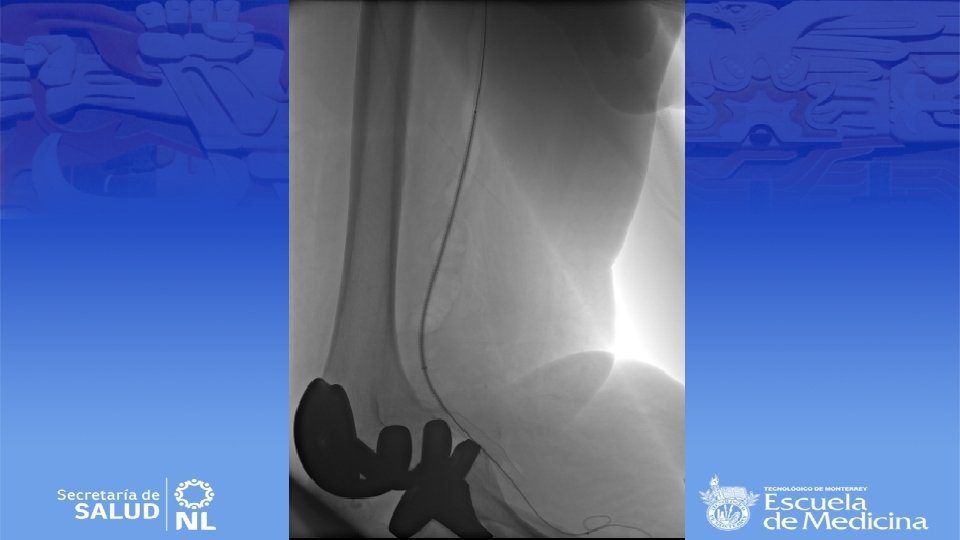

Diagnostico • Ultrasonido Doppler, Angiotac, angioresonancia • Arteriografía es mas apropiada para sintomatología aguda

Cirugía de emergencia • Establecer viabilidad de la extremidad (buscar deficiencia motora o sensitiva) • Sin daño se inicia anticoagulación sistémica y se realiza angiografía en busca de algún vaso viable para bypass. • Si no se encuentran se realiza trombolisis dirigida • Si se encuentra daño el bypass sigue siendo el mejor tratamiento • Si no hay vaso viable se realizara trombectomía tibial

Cirugía endovascular • Para pacientes con alto riesgo quirúrgico • Deben de tener al menos 2 cm de arteria proximal y distal sin patología para anclar la endoprótesis • Se repite la angiografía durante el procedimiento para selección de la endoprótesis correcta • Debe de ser 10 a 15% mas grande que el diámetro del vaso